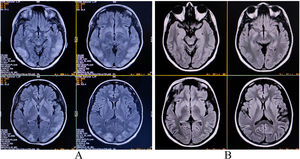

While entering the clinic, she could not find the entrance as if she was blind. Neuroophthalmological examination revealed that her pupils were equal (3 mm) and reacted normally to light and visual acuities were 20/20 with −2.0 diopter spherical correction in both eyes. Contrast sensitivity and color vision (by Ishihara's chart) were normal. Although she had a full range of voluntary saccades to directional commands, she could not make visually guided saccades to objects. She had severe difficulties in grasping or reaching out for things held in front of her (optic ataxia), an inability to process several visual stimuli or multiple competing sensory stimuli simultaneously (simultanagnosia) and had inability to voluntarily shift/move her eyes to specific objects in her peripheral visual fields and to see fast-moving targets (oculomotor apraxia). All these features were consistent with a diagnosis of Bálint syndrome. The remaining neurological examination was normal. The magnetic resonance imaging of the brain revealed hyperintensities on T2 and T2-fluid-attenuated inversion recovery images involving bilateral parietal, occipital, and frontal lobes (Fig. 1A). Cerebrospinal fluid analysis for infective and immune-mediated pathologies was negative. Considering the diagnosis of PRES, she was put on high-dose intravenous methylprednisolone. Optic ataxia resolved six days after the initiation of treatment. Simultanagnosia and impaired visually guided saccades resolved after a two-month follow-up. After two months following the initial presentation, MRI of the brain normalised (Fig. 1B).

Magnetic resonance imaging of the brain revealing extensive hyperintensities on T2-fluid-attenuated inversion recovery images involving bilateral parietal, occipital, and frontal lobes, suggestive of posterior reversible encephalopathy syndrome (Fig. 1A) and resolution of those altered intensity lesions after two months following the initial presentation (Fig. 1B).